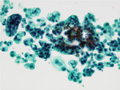

• (3)Cytology of peritoneal effusion( signet ring cell carcinoma of stomach)

Centrifugal preparation: Papanicolaou stain.The tumor cells with a large mucinous vacuole in the cytoplasm formed small papillary clusters.